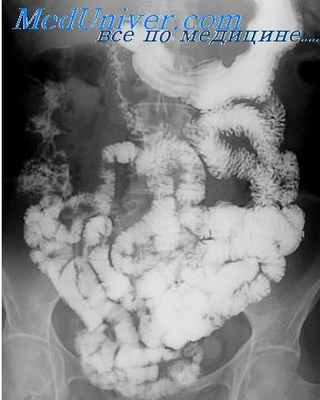

Ирригоскопия - это рентгенологическое контрастное исследование толстого кишечника. Диагностику проводят с барием или с воздухом. Что показывает рентген кишечника без бария? Проведение процедуры только с воздухом позволяет обследовать строение толстой кишки, её контуры, расположение, эластичность стенки, диаметр просвета. Чаще всего проводится ирригоскопия с двойным контрастированием, и сульфат бария, и воздух. Рентген толстого кишечника с барием показывает воспалительные процессы слизистой, а также образовавшиеся полипы, язвенные повреждения, раковые опухоли, рубцов. Также позволяет оценить функционирование кишечного клапана и всех сегментов толстой кишки.

Ирригоскопия – это рентгенологический метод исследования толстого кишечника с помощью контрастного вещества, обычно сернокислого бария, вводимого через прямую кишку.

1. Форму, расположение и диаметр просвета толстой кишки,

2. Растяжимость и эластичность кишечной стенки, функцию баугиниевой заслонки (это кишечная складка, расположенная в месте перехода подвздошной кишки в толстую. В норме она пропускает кишечное содержимое только в одном направлении – из тонкого кишечника в толстый, а при нарушении её функции отмечается заброс в обратную сторону. При ирригоскопии это хорошо видно по движению контраста).

3. Функциональное состояние разных отделов кишечника

4. Рельеф слизистой оболочки. Этот показатель имеет решающее значение в диагностике язвенных поражений, дивертикулёза, свищей, опухолей, а также врождённых аномалий развития и рубцовых сужений толстого кишечника.